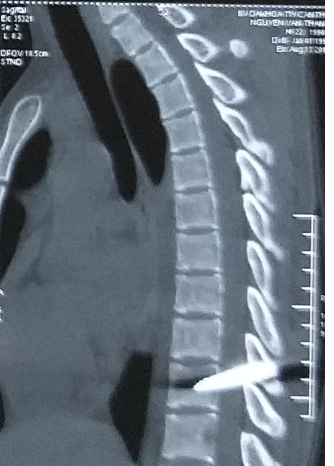

Sau khi nhập viện, các BS tiến hành chụp CT-Scan cho thấy bệnh nhân bị mũi dao đâm xuyên tủy 4cm làm rách màng tủy và một phần bản sống D11.

| Hình ảnh mũi dao đâm xuyên tủy bệnh nhên T. |

Đây là trường hợp khó kèm nguy cơ tai biến cao, các BS phải bóc tách cơ, dùng kìm gắp mũi dao kim loại ra khỏi bản sống D10, tiến hành cắt cung sau D10 và một phần bản sống D11, giải áp chèn ép tủy; vá kín màng cứng, lấy máu tụ màng tủy, cầm máu tủy, đặt ống dẫn lưu dưới cơ, đóng vết mổ từng lớp.